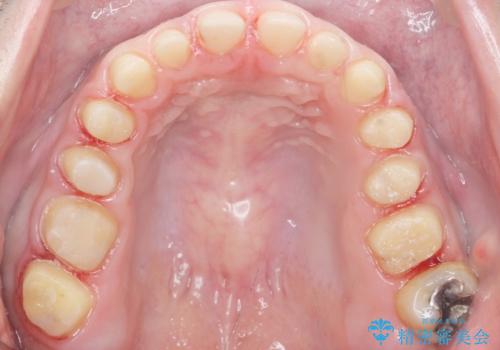

- K-POP(Kポップ)アイドルのような歯にしたいと希望され来院された患者様です。

矯正を途中でやめてしまったとのことで、歯に矯正の接着材が残っており着色も顕著でした。

奥歯の咬合面にはレジンが盛られた状態でした。